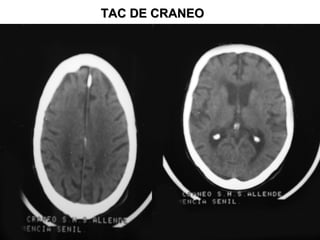

Imágenes en tomografía. Tumor y

edema.

Imágenes en TAC.

TAC: imágenes hiperdensa, isodensas

TAC DETAC DE

CRANEOCRANEO

TAC DE CRANEOTAC DE CRANEO